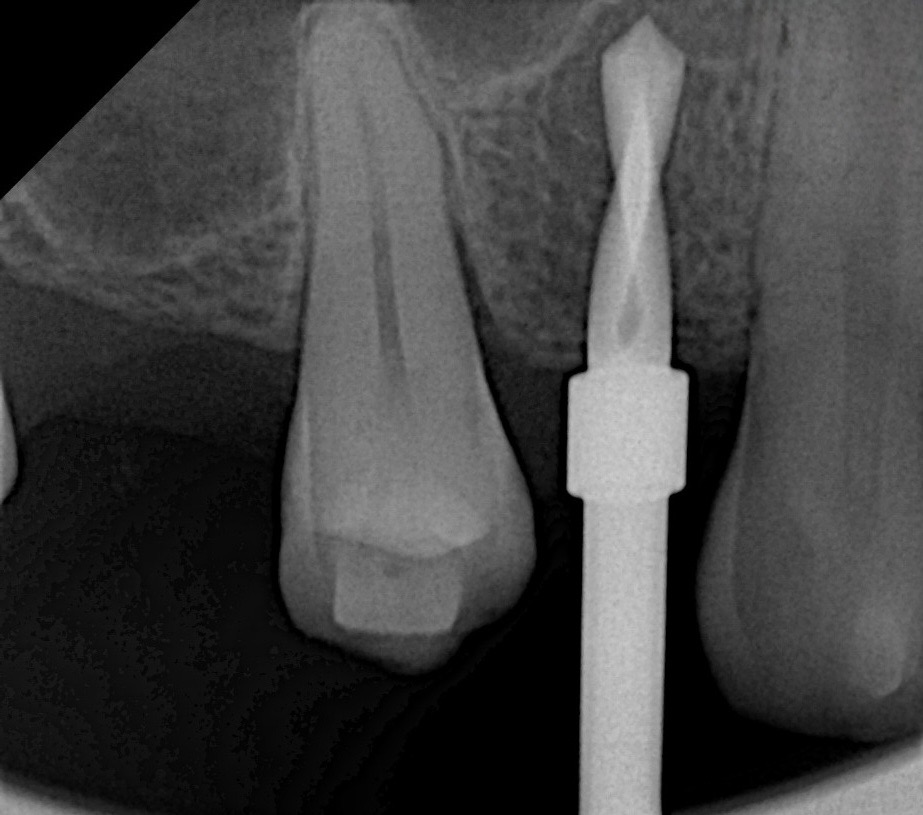

A Swiss-made tapered implant (4.1 × 10 mm) was inserted into the prepared osteotomy with 40 Ncm torque (Fig 4). The implant apex extended slightly into the augmented sinus cavity, achieving excellent primary stability and favorable bone compression.